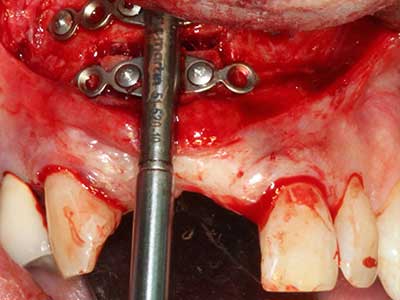

Indication: Preparations close to nerve tissue

Indication: Apical resection

When surgical procedures are performed on bone in the immediate vicinity of sensitive structures such as blood vessels or nerves, rotary instruments pose a significant risk of iatrogenic injury. Piezoelectric devices can be helpful for preparation of bone covers and removal of hard tissue close to nerves, particularly for exposure of nerves after iatrogenic injury but also during nerve lateralization for resective and reconstructive procedures or implant placement (Fig. 17-20). Light contact between the piezotip and the nerve does not generally result in damage but proceeding incautiously with saw-like motions or attachments where a residual bone substrate remains may cause temporary or even permanent nerve damage. However, the risk of damage is considered to be substantially lower than when using saws or milling instruments (Pereira, Gealh et al. 2014).